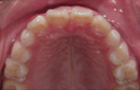

飛び出して持ち上がってしまっていた前歯が降りてきました。

横向き寝やうつぶせ、頬杖などに気をつけて治療をし、V字型だった歯並びが本来のU字型になってきました。

これで永久歯を抜かないで治療することができるようになりました。飛び出していた前歯がだんだん咬みあってきました。